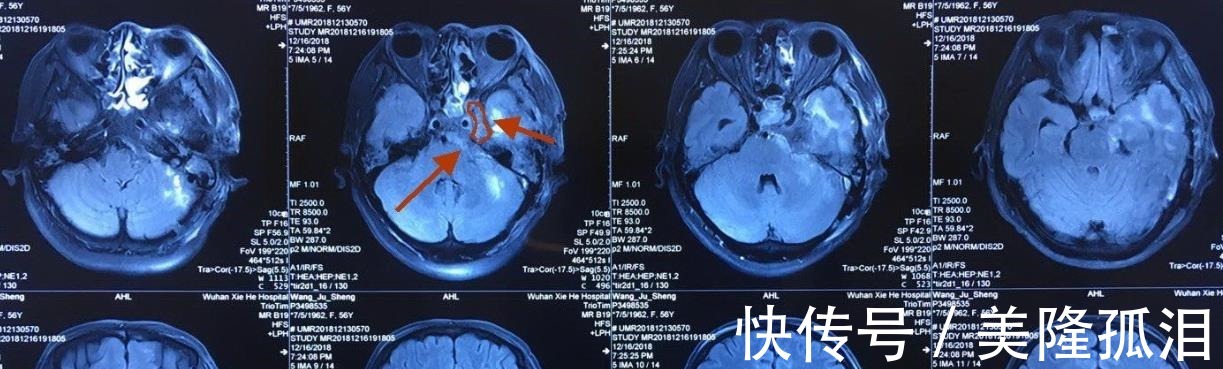

其次,磁共振成像的简称是MRI,是医学影像学检查中的成像原理比较复杂的一种技术,它的基本原理是将人体置于特殊的磁场当中,用无线射频脉冲,激发人体内的氢质子。引起氢质子发生共振,并且吸收能量,在停止射频脉冲后,氢质子在特殊的频率,发出微弱的电磁信号,探测器可以捕捉到这种微弱的电磁信号,并且通过电子计算机的处理转换得到人体内部的组织和器官的图像。因为人体的组织细胞中含有大量的水分子,它通过利用人体的氢原子在磁共振仪器中产生共振,在公证的过程中所传递出来的信息信号。核磁共振检测主要是通过高能电子计算机进行采集方式来产生磁共振动的信号再通过数字重建技术的方式转换成图像。

另外,核磁共振成像检查,目前已经成为一项常见的影像检查方式,它不会应用到放射线,因此是一个安全性比较高的检查,不会对人体的健康造成影响。但是核磁共振同时还有检查的禁忌症,比如有心脏起搏器的患者禁止检查,因为核磁共振可以多方位、多序列成像,对软组织分辨率极高,但对显示钙化和气体性的病变比较差。1、价格昂贵,会造成不必要的浪费核磁共振的检查仪器设备全套买下来很有可能要大几百万,做一次检查要1千以上,但该检查是按照检查的部位收费的,若进行全面检查,那真不是一个小数目,对于收入平庸的家庭来说价格上接受有点困难。当然对于患者必须进行核磁共振检查的,也要听从医生的安排了,毕竟生命大于一切,及早确诊,及早治疗。另外,如果是可以用CT所能检查的项目,那些非常为患者着想的医生往往也不会推荐核磁共振这项检查的,做到不必要的浪费。